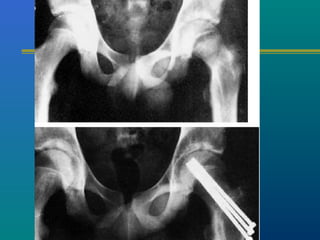

SLIPPED CAPITALSLIPPED CAPITAL

FEMORAL EPIPHYSISFEMORAL EPIPHYSIS

A true adolescent problem

Gradual or acute slip

through the capital

femoral physis

Insitu pinning

Reduction and fixation

Corrective osteotomies

Insitu pinning

Image intensifier control

Cannulated screw fixation